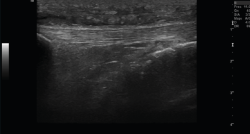

1. Ligamentos

Tanto el ligamento lateral interno (LLI) como el ligamento lateral externo (LLE) pueden ser valorados por ecografía (Figura 7).

Figura 7. Corte coronal de una ecografía de rodilla. A: engrosamiento del ligamento lateral externo en la inserción proximal por un esguince de grado I; B: engrosamiento del ligamento lateral interno.